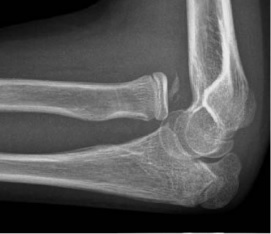

4. 발생

팔꿈치는 유아기 및 청소년기에 걸쳐 뼈가 만들어지는 중심(골화 중심)의 역동적인 발달을 겪는다. 방사선 사진에서 소아 팔꿈치를 평가할 때 골단 성장 중심의 출현 및 유합 순서가 외상성 골절이나 골단 분리를 정상적인 발달과 구별하는 데 매우 중요하다.[16] 출현 순서는 CRITOE라는 약어로 이해할 수 있는데, 이는 다음 뼈들이 나타나는 순서를 의미한다.

이러한 골단 중심은 청소년기에 융합되며, 내측 상과와 주두가 마지막으로 융합된다. 융합 연령은 골화보다 더 가변적이지만, 일반적으로 각각 13, 15, 17, 13, 16, 13세에 발생한다.[16] 또한, 지방 패드 징후의 존재로 관절 삼출액의 존재를 추론할 수 있는데, 이는 일반적으로 생리학적으로 존재하지만, 액체에 의해 상승될 때는 병리학적이며, 뒤쪽에 있을 때는 항상 병리학적인 구조이다.[17]